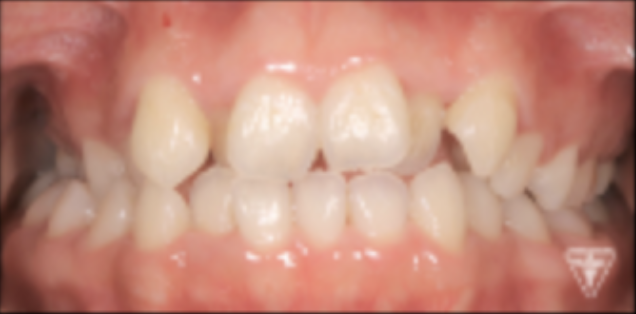

治療前

治療後